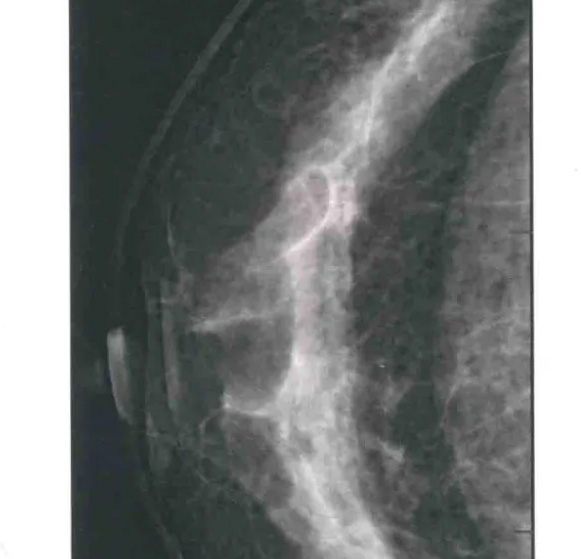

二、圖像顯示要求,含乳腺的基底部及內(nèi)外側(cè)乳腺組織,需要顯示胸肌前緣或胸壁。頭尾位與內(nèi)外斜位乳頭后線(xiàn)長(zhǎng)度差≤1厘米;顯示實(shí)質(zhì)后的乳腺組織,乳頭位于切線(xiàn)位,乳腺組織重疊;雙側(cè)乳腺頭尾位照片相對(duì)放置,則兩側(cè)乳腺呈球形;影像密度和對(duì)比度良好,能顯示0.1毫米細(xì)小鈣化,清晰沒(méi)有偽影異物、運(yùn)動(dòng)偽影和切割偽影等。